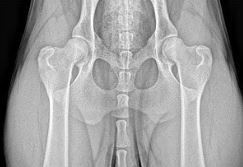

In 1974, Tina Barber began developing a unique line of German Shepherds at Shiloh Shepherd Kennels in New York State. Her goal was to preserve the type of dog she remembered from her childhood in Germany; dogs who are good family companions, exceptionally intelligent, mentally sound, big and beautiful – similar to Chuck Eisenmann’s dogs from The Littlest Hobo. After years of breeding and training German Shepherds, she chose to start reviving the breed by using the Thuringer lines for intelligence and the mountain shepherd lines for size and soundness. After years of selective breeding, Ms Barber separated her foundation stock from the AKC in 1990. When it came time to choose the name for the new rare breed, the FIC pointed out that most people knew her lines by the kennel name, and thus Shiloh Shepherd was chosen. Today four main lines are recognized, named for the bitches who were instrumental in developing the breed. Kari brought considerable intelligence and fluid movement, Ursa had a beautiful and sound body, Ria contributed the broad head and softer temperament and Sabrina added in the heavier bone structure and plush coats. Knowledge of these dominant lines along with their faults and virtues is paramount when breeding Shilohs; just as crossing these lines correctly can create sound, well formed Shilohs, crossing them incorrectly can result in hip, back or temperament problems. Starting in 1990, Shilohs were registered through the FIC as a separate breed. At this time, Ms. Barber formed The Shiloh Shepherd Dog Club of America (SSDCA, Inc.). After the FIC showed some difficulty with standards verification, Ms. Barber and the SSDCA decided to open their own registry in 1991, The International Shiloh Shepherd Registry (ISSR). After some documentation issues became evident, The Complete Computer Place (TCCP) was contacted in 1992 to design a program to process registry data for the ISSR. They also maintain an ancestry database to assist in calculating health and temperament factors within this limited gene pool. The SSDCA was dormant during part of 1997 to support the opening of a new breed club, The International Shiloh Shepherd Dog Club (ISSDC). When the ISSDC stopped working with the ISSR and opened their own registry, the ISSDC/r, the SSDCA reactivated and has been maintained as the breed club for the ISSR. The ISSDC and its registry closed in 2001. The Shiloh Shepherd Breed Association (SSBA) was opened shortly after to assume its registry functions. The National Shiloh Breed Registry (NSBR) was established in 2001 with an emphasis on shared knowledge and giving more control over breeding to the individual breeder. The Shiloh Shepherd Registry (TSSR) was opened in 2002 with a focus on health requirements. The ISSDC was reorganized in 2004 as a unifying breed club for the SSBA, NSBR and TSSR registries. During recent years, many breeders have focused diligently on health and consequently you will often see health testing that is above and beyond requirements of any registry or club.